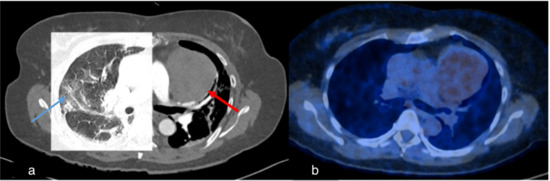

Figure 5.

Case 2, 60-year-old female. (a) Initial chest CT to clarify pulmonary embolism or COVID-19 findings showed pneumonic infiltrates of indeterminate appearance for COVID-19 (blue arrow) and revealed a large mediastinal mass (red arrow). (b) PET/CT demonstrated mild FDG-uptake, making the diagnosis of thymoma more likely than lymphoma.